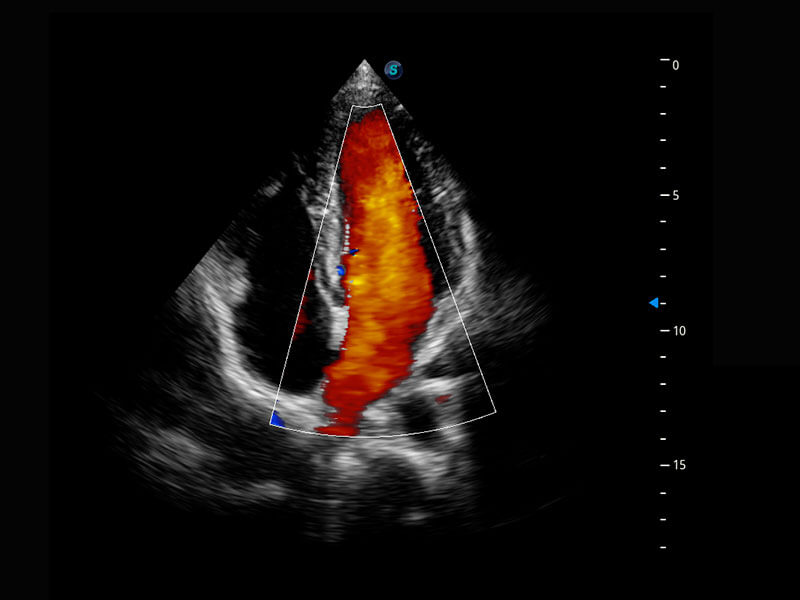

早孕筛查

P60在胎儿早孕期超声筛查中为您带来优异的图像质量。

• 早孕-胎心

• 高分辨率容积成像-早孕胎儿

• 胎儿体循环

• 光影成像-孕囊